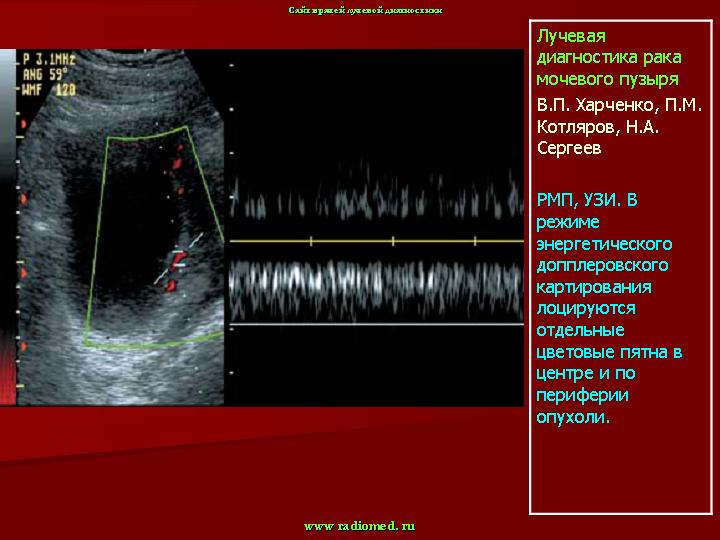

При подозрении на опухоль мочевого пузыря обследование больного следует начинать с ультразвукового исследования. При этом используют трансабдоминальное, трансректальное и внутрипузырное исследование. Оно всегда должно проводиться при заполненном мочевом пузыре. При этом можно определить и документировать объем мочевого пузыря, наличие и количество остаточной мочи после мочеиспускания, наличие опухолевых разрастаний в пузыре, их локализацию, размеры, количество, взаимоотношения с шейкой пузыря, реже - степень прорастания стенки, т.е. стадию заболевания.

При выполнении трансабдоминальной ультрасонографии большие трудности возникают при выявлении опухолей, расположенных на передней стенке мочевого пузыря. Лишь в тех случаях, когда величина опухоли превышает 3 см, ее можно обнаружить при ультразвуковом наружном сканировании. Однако оценить степень местного распространения опухоли этой локализации с помощью трансабдоминальной ультрасонографии не представляется возможным. Большинство исследователей, изучавших информативность трансабдоминальной ультрасонографии в определении степени выраженности местного распространения злокачественного процесса у больных раком мочевого пузыря, отмечают существенные ограничения этого метода [4, 14, 19]. Показано, что трансабдоминальная ультрасо-нография является недостаточно информативным методом распознавания начальных стадий рака мочевого пузыря, особенно в тех случаях, когда опухоль локализуется на передней стенке органа [6, 17, 23, 25]. Это обусловлено препятствиями по ходу ультразвукового луча при выполнении трансабдоминальной ультрасонографии (большой массив тканей, лонное сочленение). Они затрудняют визуализацию всех отделов мочевого пузыря. В этих случаях применение эндовезикального ультразвукового сканирования оказывает существенную помощь в диагностике.